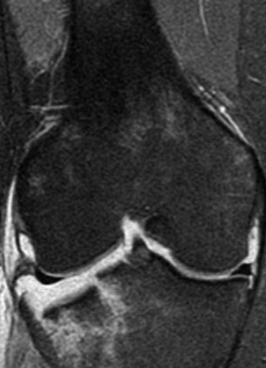

Uso de RM en fracturas

Lesiones ligamentaria o tendinosa

Rx ocultas